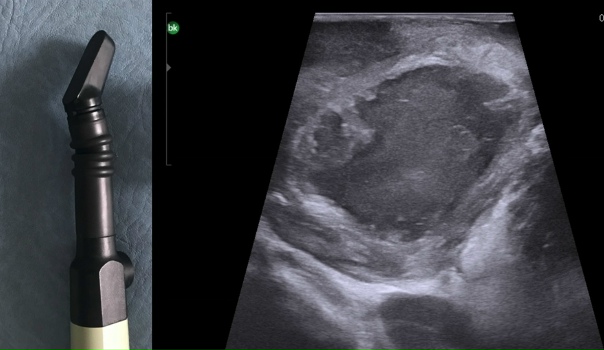

УЗИ при абсцессе малого таза: Диагностика и лечение